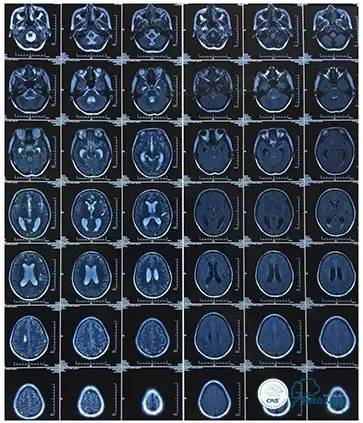

MRI T1

MRI T2

2016-5-19 MRI

2016-05-20 MRV

磁共振黑血系列